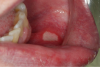

Herpes Simplex (Figure 2). Herpes simplex virus causes both primary and recurrent oral disease. The primary event, herpetic gingivostomatitis, is most common among children and young adults in the general population and it is also seen in young people with HIV infection. Herpetic gingivostomatitis presents as ulcers and vesicles on the gingiva as well as elsewhere on the oral mucosa. The lesions are accompanied by fever and complaints of pain and loss of appetite. Recurrent herpes simplex may involve the lips or the intraoral mucosa. Lip lesions appear as small vesicles that rupture, ulcerate, and then form a crust. Recurrent, intraoral herpes simplex starts as small crops of vesicles on the hard palate or gingiva that rupture to produce small, painful, merging ulcers. Patients with active, puss-filled ulcers should receive only palliative treatment and rescheduled for treatments that can be delayed until the lesions are crusted.

The oral lesions are usually confined to the keratinized mucosa, although lesions may appear on the dorsal surface of the tongue. The buccal mucosa and lateral margin of the tongue are very rarely involved. The lesions may be trivial and self limiting or, occasionally, troublesome, extensive, and persistent. Lesions that are slow to resolve can be treated with acyclovir, 1000 to 1600 mg daily for seven to ten days. Topical acyclovir is not effective in treating intraoral lesions and may not be effective in treating herpes labialis. Occasionally, herpes labialis is resistant to treatment with acyclovir; these lesions may respond to phosphonoformate.

Figure 2. Herpes, lips (courtesy of dentalcare.com)

Figure 2